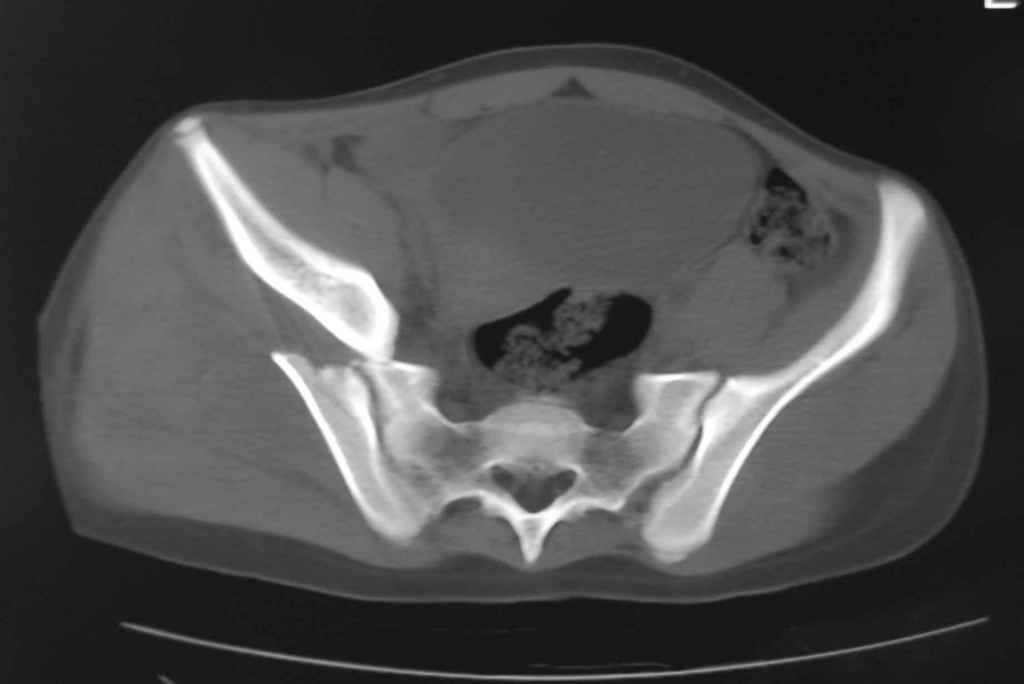

Принципиально важно видеть все срезы КТ через вертлугу, так как тактика лечения будет в первую очередь обусловлена характером перелома ветрлужной впадины, во вторую - вертикальным смещением таза ( где варианты - от банального скелетного вытяжения до ВЧКО или накостного остеосинтеза - в основном зависит от пресловутой "позиции кафедры")

Уважаемый Алексей, на представленных Вами снимках имеется вертикально-нестабильное повреждение тазового кольца без повреждения вертлужной впадины. Учитывая это, а так же растущий возраст ребенка я бы выбрал аппарат внешней фиксации в виде кольцевой опоры, т.к. не смотря на оскольчатый перелом крыла в переднем отделе можно ввести минимум 2 стержня + 1-2 надвертлужно. Этого будет достаточно чтобы "зацепится", выполнить репозицию и дальнейшую фиксацию. Перелом шейки по моему лучше прооперировать 3 канюлированными винтами по АО.